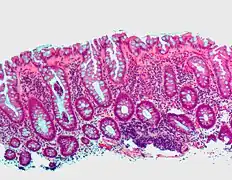

Tubular adenoma | 2% at 1.5cm[15] | Low to high grade dysplasia[16] | Over 75% of volume has tubular appearance.[17] | ![]() |